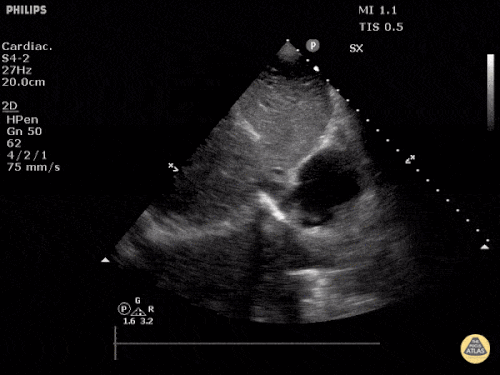

Parasternal uzun aks

Sol ventrikül fonksiyonunun değerlendirilmesi

Sol ventrikül (LV) fonksiyonu dört pencerenin tamamında değerlendirilebilir; ancak genellikle parasternal uzun aks görüntüsünde en kolay şekilde incelenir. Değerlendirme iki şekilde yapılabilir:

Görsel (subjektif) tahmin

EPSS (End Point Septal Separation) ölçümü

Çok sayıda çalışma, acil hekimleri ile kardiyologlar arasında global kardiyak fonksiyonun görsel değerlendirilmesi açısından yeterli uyum olduğunu göstermiştir.

RUSH muayenesinde genellikle ejeksiyon fraksiyonunun tam yüzdesine odaklanmak yerine, sol ventrikül fonksiyonunu geniş kategoriler halinde sınıflandırırız:

Azalmış sol ventrikül fonksiyonunu düşündüren hızlı ve pratik bulgular şunlardır:

Sol ventrikül kavite çapının sistolde yaklaşık üçte bir oranında küçülmemesi

Miyokardın sistol sırasında yeterince kalınlaşmaması

Mitral kapağın ön yaprağının diyastolde septuma yaklaşmaması

Buna karşılık hiperdinamik bir kalpte, sistolün zirvesinde ventrikül duvarlarının neredeyse tamamen kollabe olup birbirine temas ettiği izlenir.